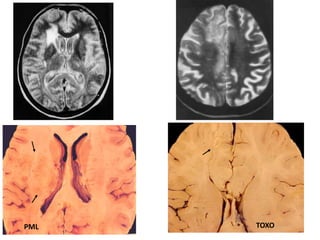

PML - Pathology

Gross: Multiple, focal white matter softening (resemble MS)

Microscopy :

• Infects oligodendroglia (astrocytes, neurons - not infected)

• Intranuclear basophilic inclusions

• Abnormal astrocytes - Tumor-like

• With HIV + PML Extensive necrosis

Microglial reaction

PML TOXO